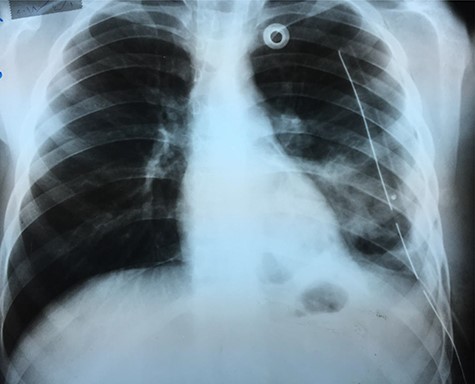

Chest X-ray (Fig. 1) showed an increased density in the left lower zone of the lung. Forty-eight hours later, the patient arrived at the ER along with the computed tomography (CT) scan (Fig. 2). He was in a very poor general condition with pallor, severe dyspnea and clouding of consciousness. Physical examination showed the absence of the left lung sounds, shifted apex beat of the heart to the right and a thready pulse and a blood pressure of about 80/40 mmHg.